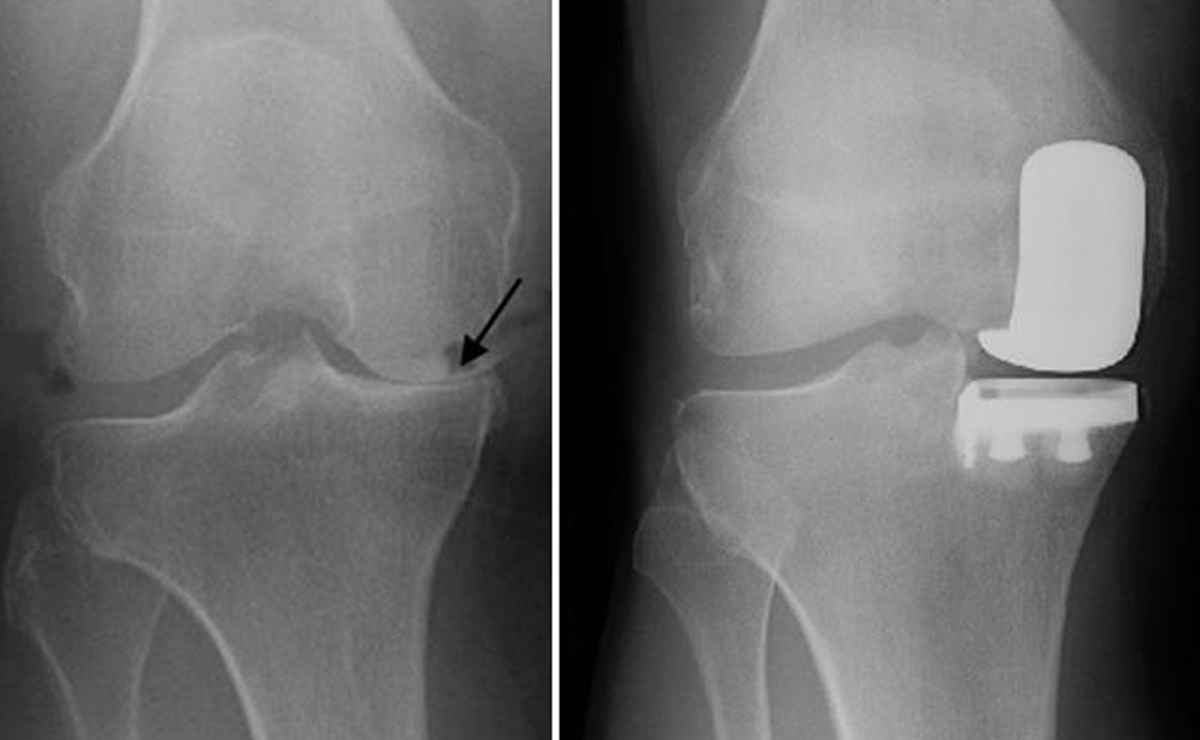

Partial Knee Replacement is a surgical option for patients in whom arthritis or damage is confined to only one compartment of the knee joint—most commonly the inner (medial) side. Unlike total knee replacement, this procedure preserves healthy bone, cartilage, and ligaments while replacing only the damaged portion of the knee with an artificial implant. Because the healthy structures of the knee are retained, patients often experience more natural knee movement after surgery.

This procedure is ideal for selected patients who have localized knee pain, good knee stability, and minimal deformity. Partial knee replacement involves a smaller incision, less tissue disruption, reduced blood loss, and faster recovery compared to total knee replacement. Patients often experience less post-operative pain and can return to daily activities more quickly. With proper patient selection and rehabilitation, partial knee replacement offers excellent pain relief, improved mobility, and long-term functional benefits.